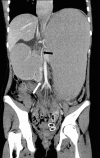

Background: Superior mesenteric artery (SMA) syndrome is an uncommon condition resulting in partial small bowel obstruction because of external compression of the third portion of the duodenum between the SMA anteriorly and the aorta posteriorly. SMA syndrome often presents with postprandial nausea, bilious vomiting, and abdominal pain with associated weight loss. Onset of symptoms can be acute (occurring in the setting of rapid weight loss because of trauma/surgery) or can be vague and chronic over many years.

Case reports: We present two cases of female adolescents who presented with symptoms of duodenal obstruction attributed to SMA syndrome. Both failed conservative treatment with weight gain and underwent successful laparoscopic duodenojejunostomy procedures with resolution of duodenal obstruction.

Conclusion: In the differential diagnosis of persistent nausea and bilious vomiting, even in the setting of an eating disorder, SMA syndrome should be considered. Upper gastrointestinal examination is the primary modality for diagnosing SMA syndrome, but ultrasound is an inexpensive, rapid screening tool for patients with unexplained abdominal pain. Abdominal computed tomography may also be helpful in selected patients. Conservative therapy consisting of nutritional support to enhance weight gain is usually sufficient and is accomplished with placement of a nasojejunal feeding tube past the point of duodenal compression. When conservative therapy fails, laparoscopic duodenojejunostomy can provide definitive relief of the obstruction.